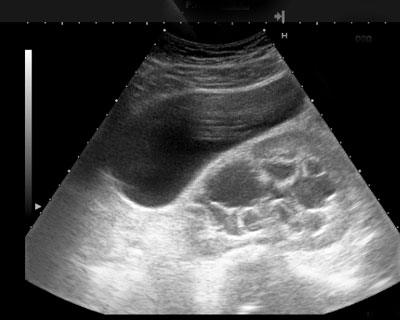

Abdominal

Abdominal is an imaging method that used X-ray to create the structure inside the body and images of organs. It has the machine transmit high frequency sound waves that reflect off body structures and the machine reflect body structures images send to a computer screen that the technician monitors to check for a potential aneurysm. It is used to examine organs in the abdominal like the liver, gallbladder, spleen, pancreas, and kidneys. It is also called gastrointestinal examination.